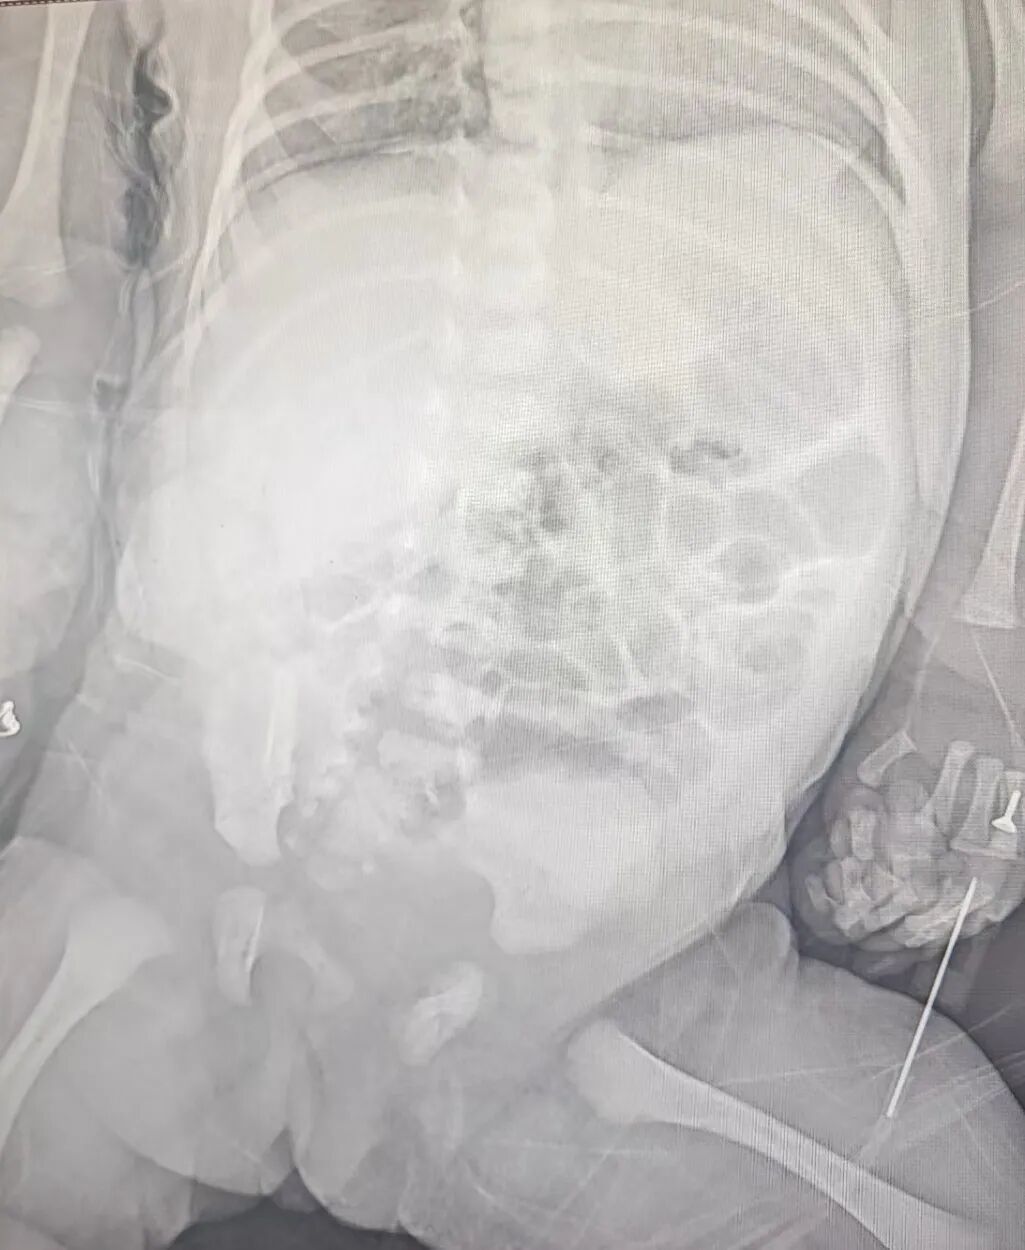

接诊后,医院立即启动多学科协作机制,新生儿外科主任宋华团队第一时间前往会诊。结合患儿胎儿期产检就发现右下腹 3 厘米大小囊性回声的病史,查体时面色及躯干部皮肤苍黄的表现,以及超声、影像等提示的各项异常,团队初步诊断为腹腔隐匿出血、肠扭转、黄疸、贫血,建议尽快手术干预。

△腹部影像提示隐蔽性腹部出血

时间就是生命。团队果断决定连夜开展急诊腹腔探查手术,争分夺秒挽救患儿生命。术中可见腹腔内大量积血,脾区有血凝块聚集,残脾断面存在大量活动渗血,确诊为新生儿自发性脾破裂这一极为罕见且危及生命的疾病!